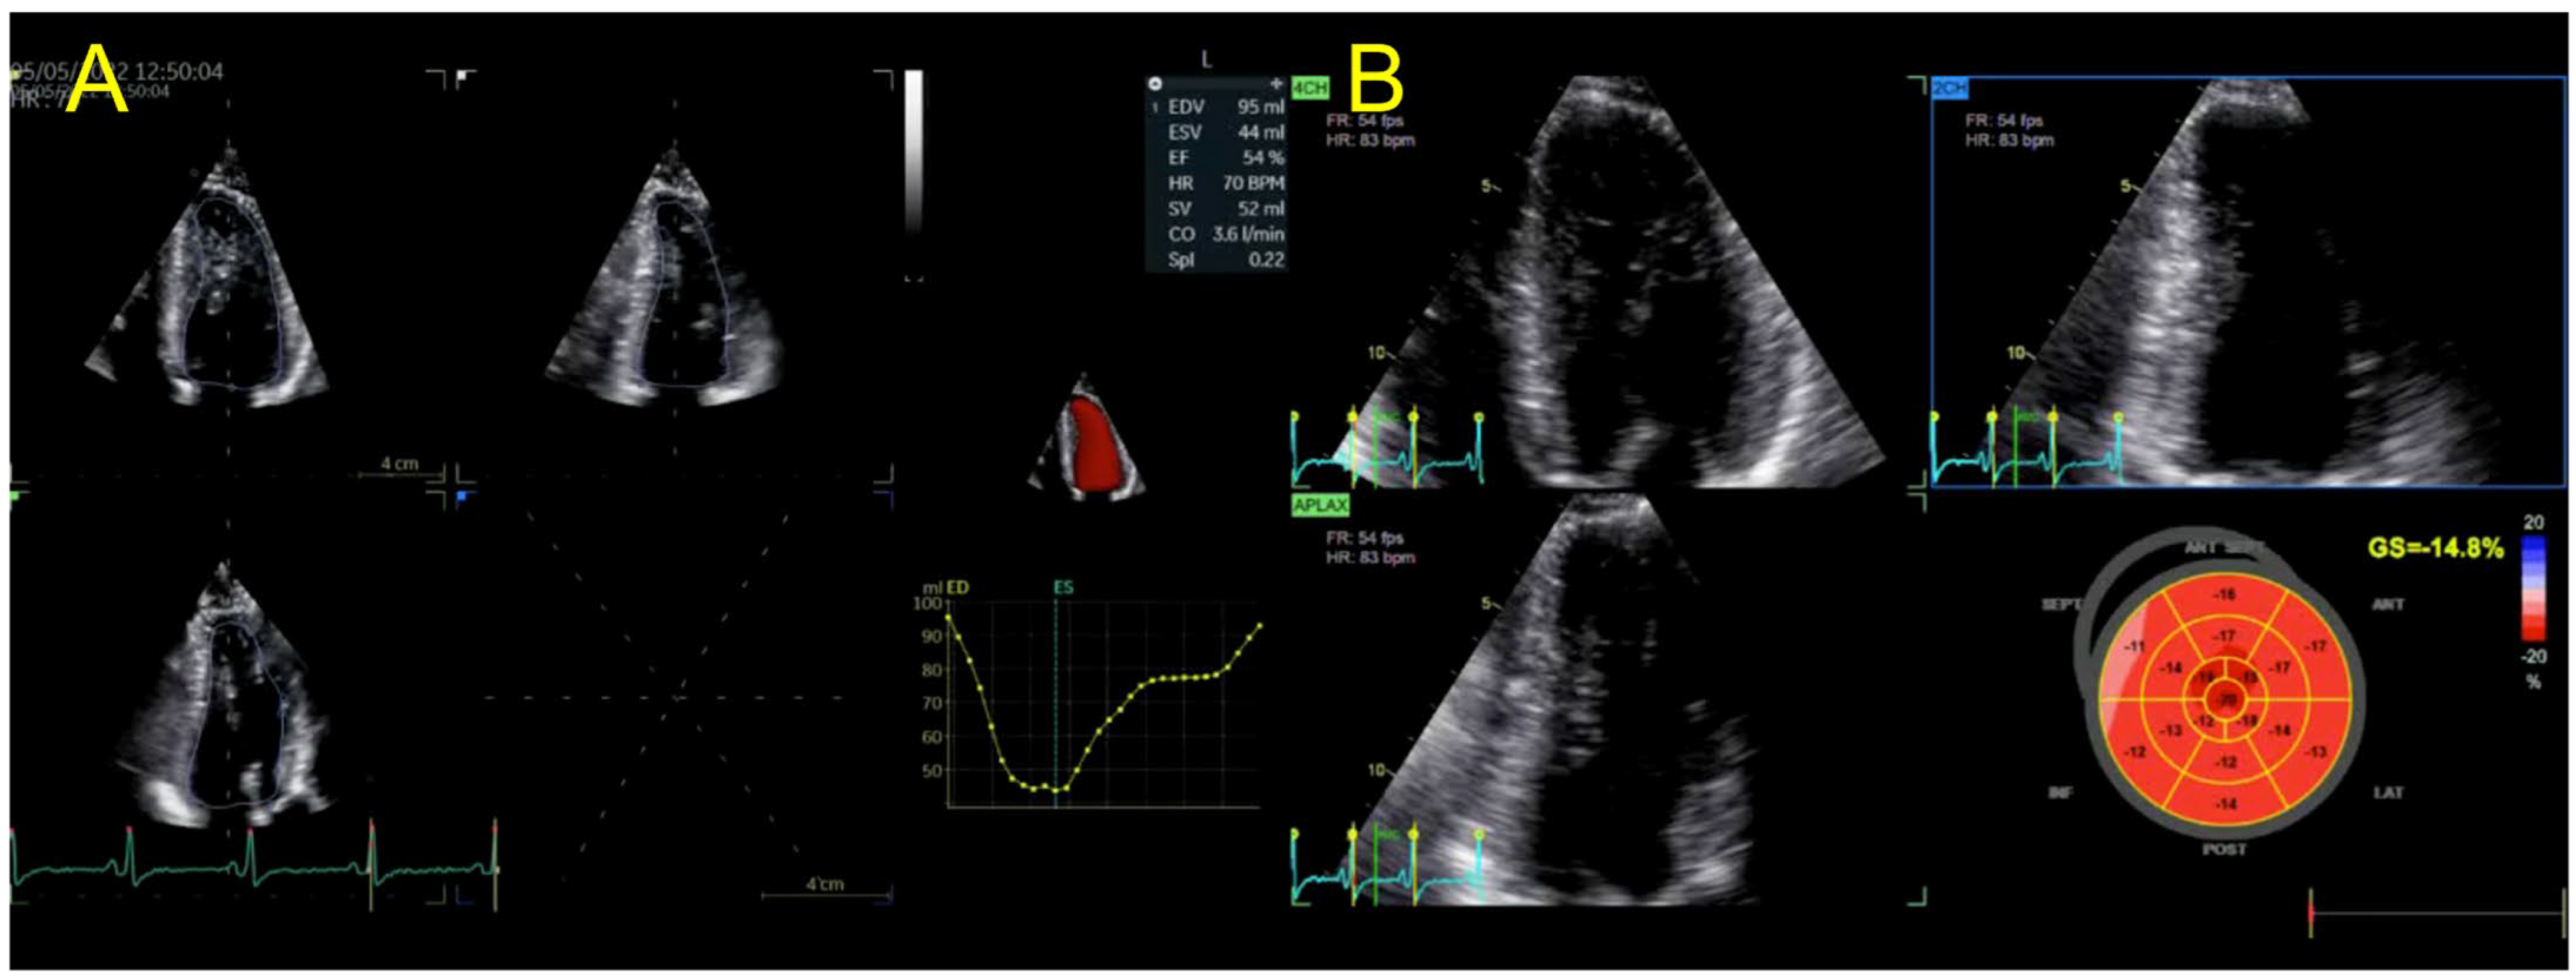

| Echocardiography | Hypokinetic non-dilated cardiomyopathy LVEF = 42% Mild mitral regurgitation IAS aneurysm | Hypokinetic non-dilated cardiomyopathy LVEF = 34% Mild mitral regurgitation IAS aneurysm | Left ventricular concentric hypertrophy LVEF = 54% |

| Cardiac magnetic resonance imaging | Hypokinetic non-dilated cardiomyopathy Left ventricular non-compaction LVEF = 50% | Hypokinetic non-dilated cardiomyopathy Regional sub-epicardial fibrosis LVEF = 41% | Not carried out |